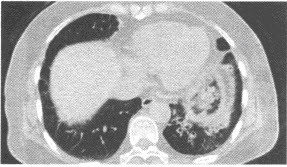

患者,女,57岁,咳嗽、咳痰两个月余,3天前咯鲜血一次,约5ml,作胸部CT扫描如图。则应诊断为()

A:周围型肺癌

B:支气管肺炎

C:中央型肺癌

D:支气管扩张

E:肺泡蛋白沉积症